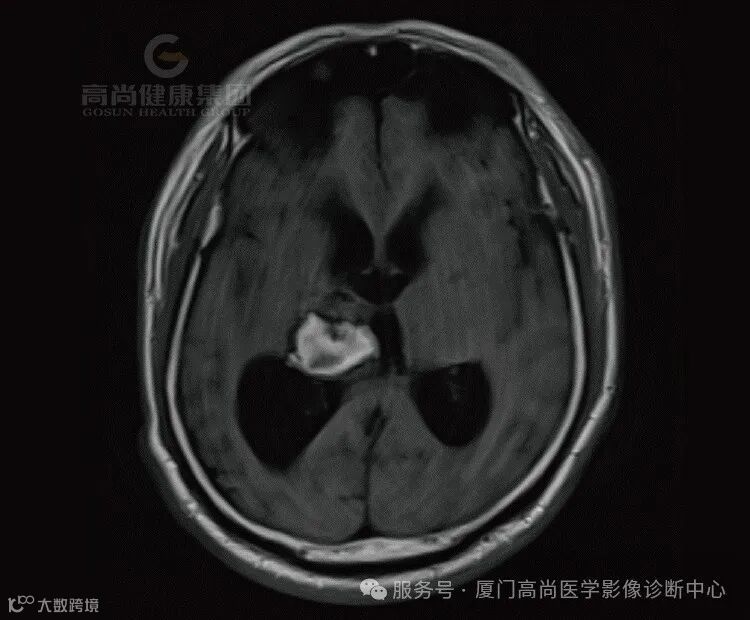

患者代诉左侧肢体无力半月余,既往高血压史。

1.右侧丘脑、基底节、放射冠区病灶,考虑脑出血(亚急性期)并破入右侧脑室,中线结构局部左偏,请结合临床。

(1)亚急性早期(3-6d):血肿中心在T1呈等信号,外周呈高信号,且高信号逐渐向中心扩展;在质子加权和T2呈低信号。

(2)亚急性晚期(1-4周):T1和T2上均呈高信号,灶周水肿,占位效应逐渐减轻。

在MRI 上血肿周围脑水肿呈 TIWI 低信号、T2WI高信号,血肿周围脑水肿一般在发病后3~4d至第1周末最显著,以后逐渐减轻。约1个月后血肿开始消退。一般在2个月左右进入囊变期,此时血肿完全吸收,周围水肿完全消失,原血肿变为脑脊液的囊腔,即软化灶(T1WI呈低信号,T2WI呈高信号),与此同时出现邻近脑室、脑沟增宽等萎缩性改变。数月或更长一段时间后,可仅残存窄带状或局灶性小囊腔,小血肿甚至可完全被胶质瘢痕代替而消失。